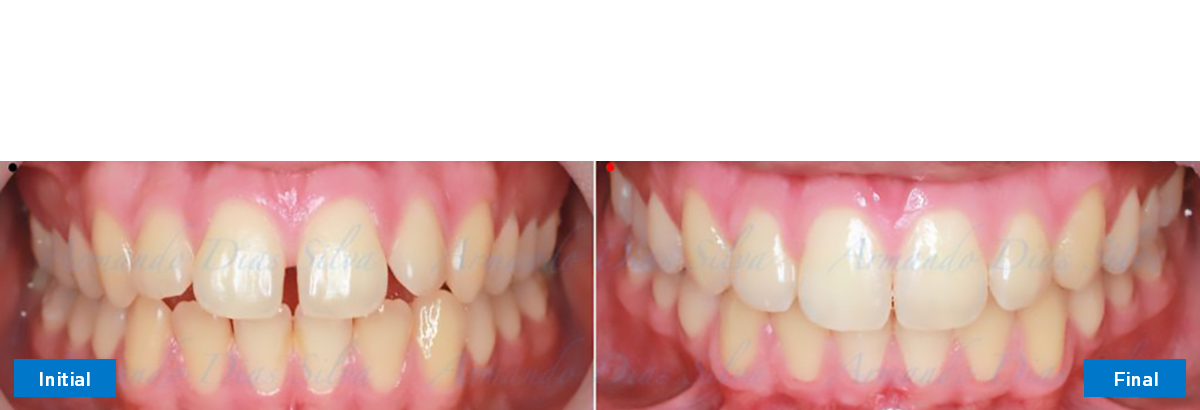

Clase II, Div. 1: Protrusión del incisivo central y espacios anteriores (SureSmile® Aligners)

Principal queja del paciente: Protrusión del incisivo central y mordida abierta. El paciente rechaza la expansión del arco palatino (MARPE) y las extracciones.

Este paciente adolescente presenta molares de Clase II y no le gusta su mordida abierta ni lo protrusivos que son sus dientes frontales. Por sus fotografías faciales, parece que su mandíbula es retrognática o le falta volumen en la barbilla. El historial del paciente también indica que existe un problema funcional al no haber guía de los incisivos.

• Diastema

• Incisivos superiores e inferiores proclinados

• Retruir los incisivos superiores

• Retroclinar los incisivos inferiores

Se logran todos los objetivos principales:

• Molares de clase I logrados con distalización y sin elásticos

• Incisivos inferiores retroinclinados, que mejoran la estabilidad a largo plazo

Retención: Arco superior retenido con retenedor transparente. Arco inferior retenido con retenedor lingual unido de canino a canino.